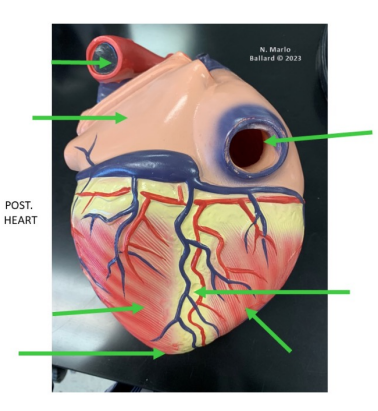

What vessels supply the myocardium?

Coronary arteries

Arise from the Ascending aorta (just above the aortic valve)

Two main arteries:

Right coronary artery

Left coronary artery

Supply oxygenated blood to the myocardium (heart muscle)